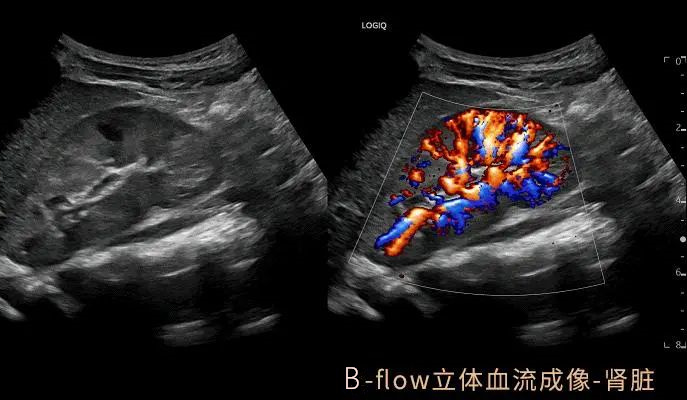

GE LOGIQ-Fortis Plus在甲状腺、乳腺、双下肢、颈部血管等检查项目方面有明显优势,对微血流的显示和弹性成像技术有全新的视野,图像更清晰细腻,血流显示立体逼真,能够实现二维条件下血流的“立体浮雕式”呈现,减少彩色血流闪烁,增强细微血管的可视化成像效果有利于临近交叉血管的边界识别。